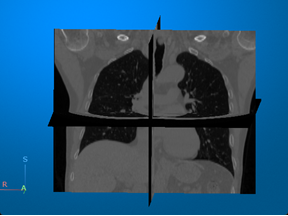

Computed tomography (CT) — Visualize 3-D patient anatomy using X-rays. |

For an example that uses this image [1], see Display Labeled Medical Image Volume in Patient Coordinate System. |

[1] Medical Segmentation Decathlon. "Lung." Tasks. Accessed May 10, 2018. http://medicaldecathlon.com/. The Medical Segmentation Decathlon data set is provided under the CC-BY-SA 4.0 license. All warranties and representations are disclaimed. See the license for details.